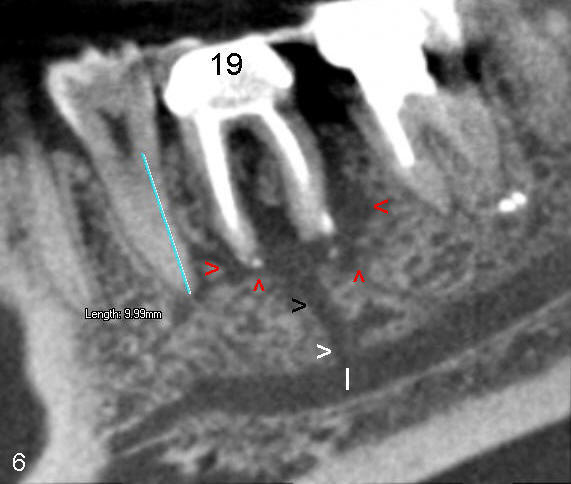

A 31-year-old otherwise healthy Chinese lady has had discomfort since RCT was done for the tooth #19 in home country ~2 years ago (Fig.1). Gutta percha (GP) appears to extrude both in mesial (<) and distal (<<) canals, surrounded by periapical radiolucency (PARL). Two carpules of 2% Lidocaine with 1:100,000 Epinephrine are used for RCT retreat. The patient does not experience any sharp pain during the first injection. Two rubber dams are used due to the short clinical crown of #19 (Fig.2,3). Fig.2 shows master cones (30/.06 M, 40/.06 D) after removal of existing gutta percha using Chloroform. It appears that extruded mesial GP remains outside the apex (< in Fig.2). It is confirmed after removing master cones (< in Fig.3). Working length is controlled by Apex locator during canal re-shaping using GT rotary files. In attempt to remove apparent GP in mesial canal(s) and extruded one outside the apex, #15 hand file is reused at WL+1mm with Chloroform for one or twice for each canal. After adjusting distal GP length, cold lateral condensation is finished with AH26 plus paste and pre-existing PFM crown is recemented (Fig.4). It is apparent that the previously extruded GP is not removed (< in Fig.4).

In fact, the traditional X-ray can also show the coronal portion of the abnormal communication (Fig.1). One or two months later, paresthesia disappears with occasional mild pain, reported by the patient. She has not returned for follow-up.